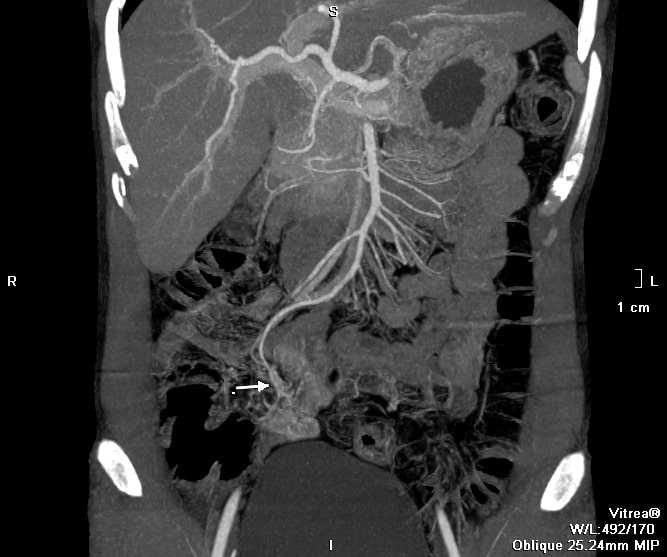

Sau hồi sức tích cực, anh C. được tiến hành chụp CT. Các bác sĩ phát hiện búi dị dạng mạch máu từ một nhánh của động mạch mạc treo tràng trên, nằm ngay trên thành ruột non, đang có dấu hiệu chảy máu. Đây là thủ phạm gây chảy máu kéo dài.

| Hình ảnh CT của bệnh nhân khi vào viện cho thấy mạch máu dị dạng gây chảy máu. Ảnh: BVCC. |